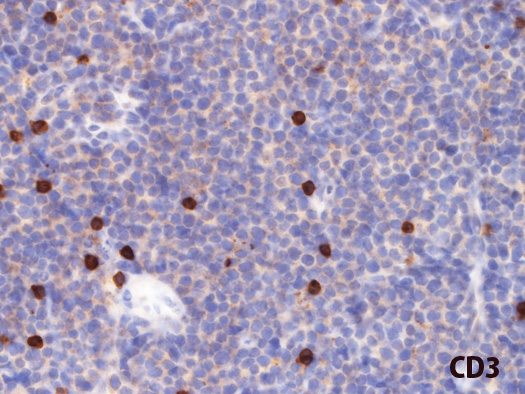

免疫染色とISH